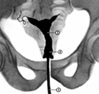

/ смотри рисунки – а, б, в, г /

Рентгенограмма при ИЦН: 1 –

3? истмико-цервикальная недостаточность (ИЦН), ОАА,

маточный зонд

2? расширенный ц/к

3? полость матки Лечение – наложение шва на ш/м в 12-16 нед.